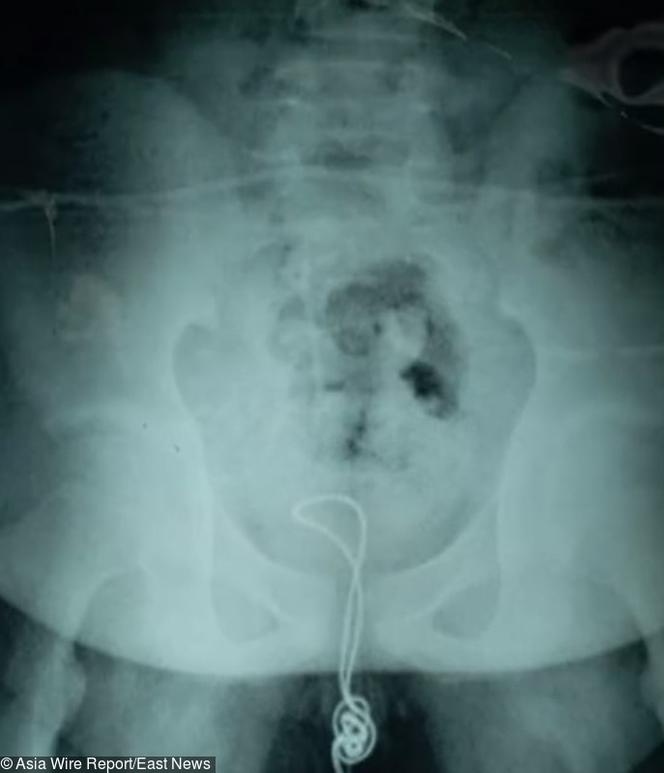

Autor: East News